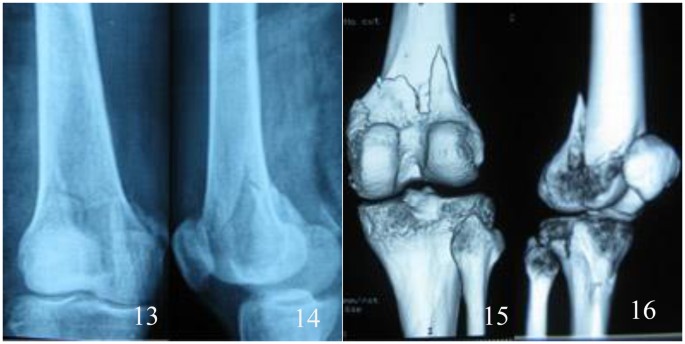

All patients were followed up for 12 to 48 months. The follow-up records of one patient of the double-plate group are shown in Figs 1–5 and those of one patient of the single plate group are shown in Figs 6 and 7. One patient in each group died one year and a half after the operation due to other causes. There were 58 patients and 60 cases of distal femoral fractures in total, of which one patient had bilateral distal femoral fractures both fixed by lateral plate and the other one with bilateral distal femoral fractures had a single plate on the right distal femur and double plates on the left. The age distribution of patients in the single-plate group and the double-plate group is shown in Table 1. There was no significant difference between the two groups (p = 0.330).

Inclusion criteria: Patients with distal femoral fractures treated with locking plate(s). Exclusion criteria: Patient with a decline of muscle strength of lower extremities. Anterior-Posterior and lateral plain film, computed tomography and 3D reconstruction of the fracture sites were performed to identify the fracture types.